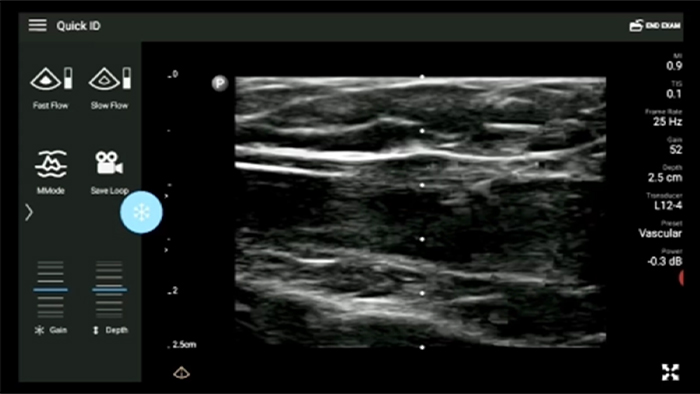

Exceptional ultrasound imaging

Lumify handheld ultrasound offers images that enhance diagnostic confidence.